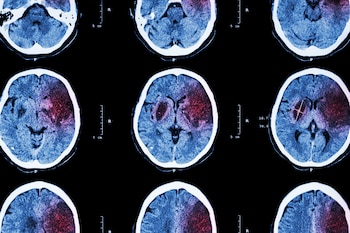

De acuerdo con varios otros informes, el riesgo de eventos cerebrovasculares (accidente isquémico y hemorragia intracraneal) se elevó después del COVID-19, y la incidencia de accidente cerebrovascular isquémico aumentó a casi uno de cada diez (o tres de cada 100 para un primer accidente) en pacientes con encefalopatía. Se ha informado un aumento similar del riesgo de accidente cerebrovascular en los pacientes que tenían COVID-19 en comparación con los que tenían influenza.

Un estudio anterior informó evidencia preliminar de una asociación entre COVID-19 y la demencia. Los datos del nuevo estudio apoyan esta asociación. Aunque la incidencia estimada fue modesta en toda la cohorte de COVID-19, el 66% de los pacientes mayores de 65 años y el 72% que tenían encefalopatía recibieron un primer diagnóstico de demencia dentro de los 6 meses de haber tenido COVID-19. Las asociaciones entre COVID-19 y los diagnósticos cerebrovasculares y neurodegenerativos han sido calificados por los especialistas a cargo del informe como “preocupantes”.